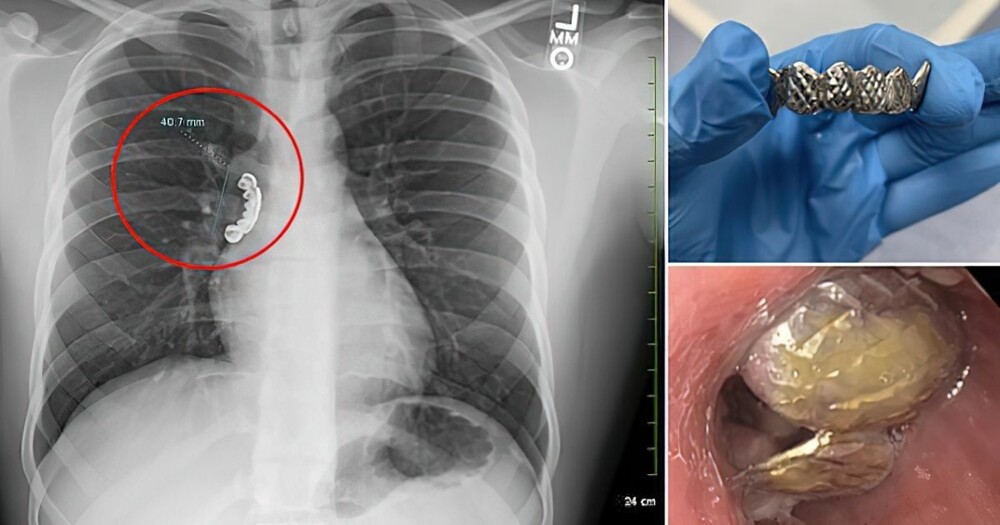

Рентгеновское сканирование показало, что 4-сантиметровая металлическая накладка застряла в правом главном стволовом бронхе, проходившем через легкие.

Врачи срочно отправили пациента на бронхоскопию, чтобы удалить инородный предмет. Эта процедура включает введение тонкой, облегченной трубки, называемой бронхоскопом, в дыхательные пути. Экстренная операция прошла успешно. Парня выписали после процедуры и курса стероидов.